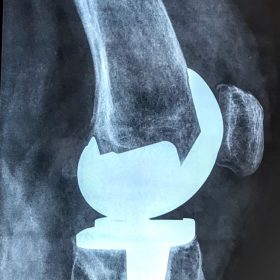

Σε αυτό το σημείο η Αρθροπλαστική Γονάτου αποτελεί μονόδρομο.